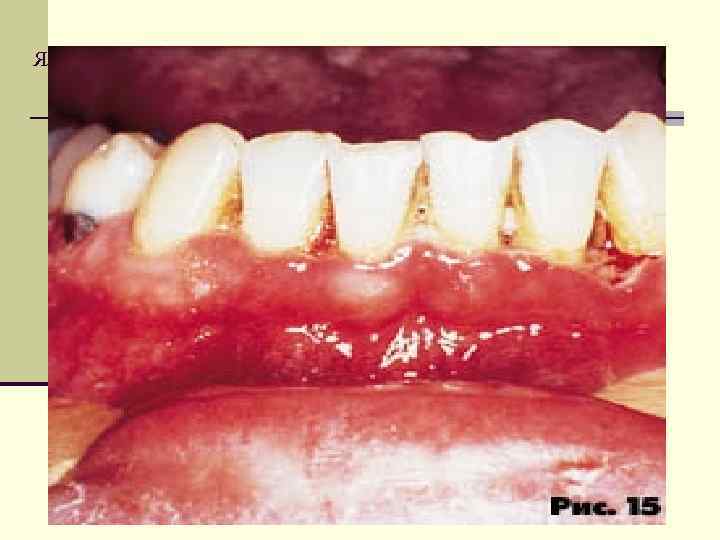

Язвенный гингивит